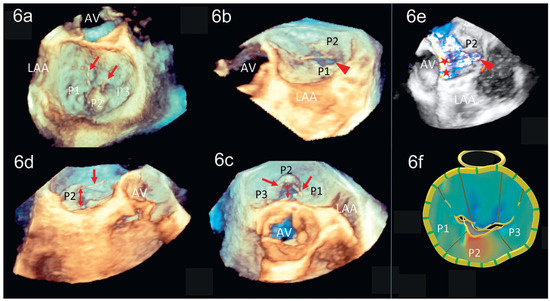

Dreidimensionale Echokardiographie zur Beurteilung der Mitralklappe

by Patric Biaggi, Christian Felix, Matthias Greutmann, David Hürlimann, Dominique Bettex and Felix C. Tanner

Using two-dimensional echocardiography, the complex anatomy of the mitral valve needs mental reconstruction into its three-dimensional shape. The power of both transthoracic and transesophageal three-dimensional echocardiography (3DE) lies in its possibility of showing the complex mitral valve anatomy in one single image, as [...] Read more.

Using two-dimensional echocardiography, the complex anatomy of the mitral valve needs mental reconstruction into its three-dimensional shape. The power of both transthoracic and transesophageal three-dimensional echocardiography (3DE) lies in its possibility of showing the complex mitral valve anatomy in one single image, as opposed to the mental reconstruction based on multiple two-dimensional images and schematic assumptions. Several 3DE modalities are used in daily life, including real time (“live”) modes as wells as postprocessed images. 3DE is of special interest in the evaluation of mitral stenosis, complex mitral valve prolapse and mitral valve prostheses. It has an established role in the perioperative mitral valve assessment during mitral valve surgery as well as during percutaneous mitral valve procedures. Limitations of 3DE are relatively low frame rates, an important learning curve as well as timeconsuming processing. Full article

Show Figures

Figure 1